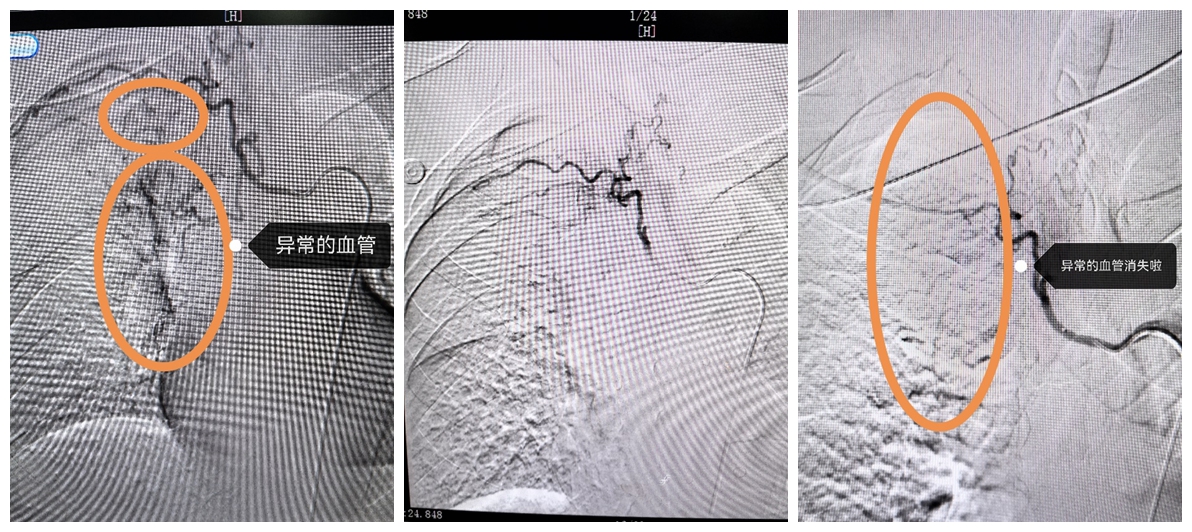

近日,黄某某因支气管扩张伴感染且住院期间反复咯血,采用了多种止血药物保守治疗后效果都不理想。经过呼吸科赵兴良主任与影像科张涛副主任详细讨论后,与患者家属充分沟通,决定采取“经导管支气管动脉栓塞术”进行治疗。

经过术前准备并完善支气管动脉CTA检查后,由医学影像科张涛副主任为其实施右肺支气管动脉介入栓塞术。手术过程十分顺利,术后患者出血状况显著改善,咯血现象逐渐停止。